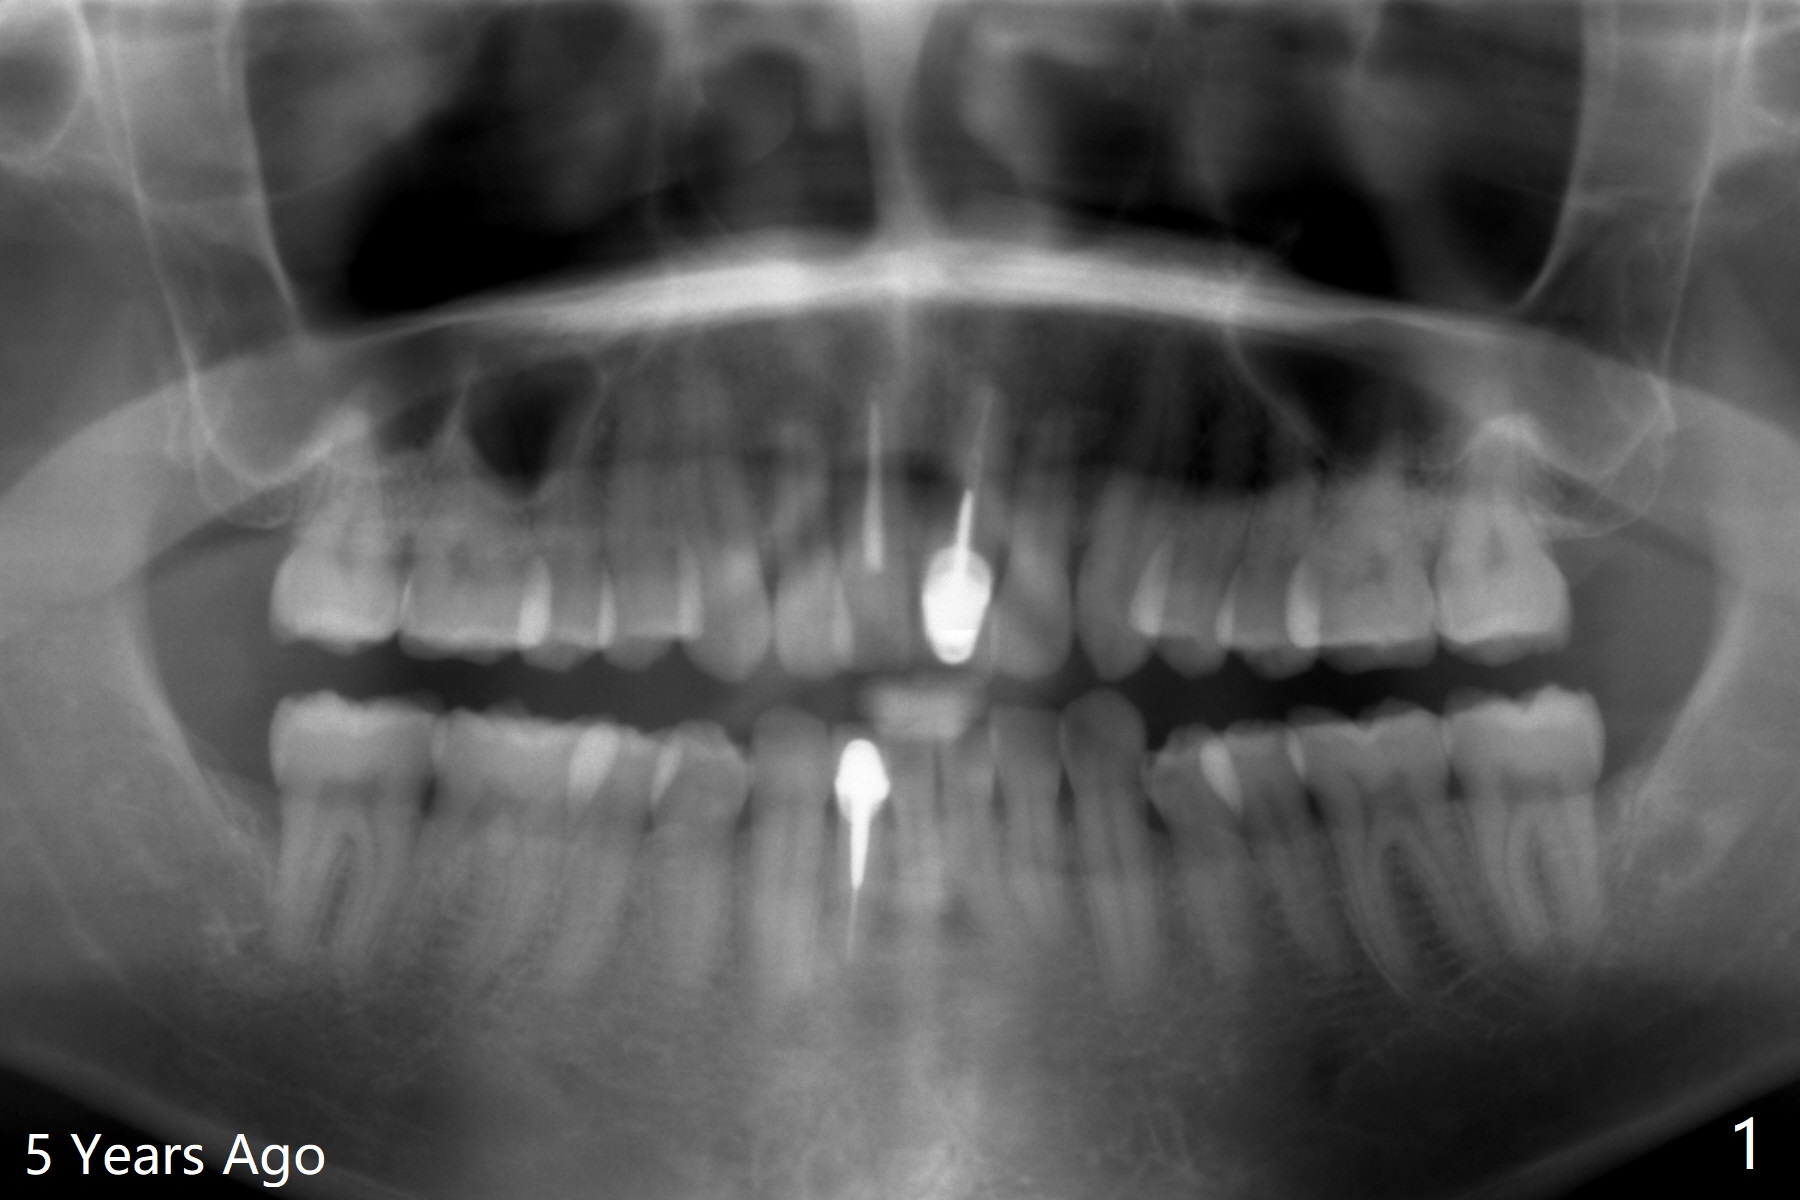

42岁男,小的时候做过矫正,据说智齿萌出后,畸形复发(图一至三)。临床检查显示:上前牙前突,下门牙拥挤,磨牙二类咬合。头颅侧位定位片证明Class II Division I Malocclusion (图四至六):SNA 84.63, SNB 76.11, ANB 8.52。 下周病人复诊,将拍摄照片,取模。正在考虑是否需要拍摄CT,排除上,下切牙是否位于牙槽骨唇侧,有利于做出拔牙决定。